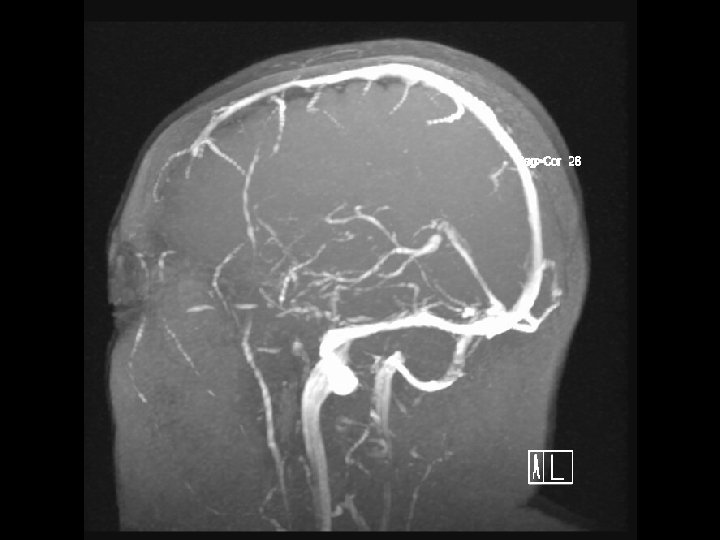

Arterial Blood Supply Arterial Blood Supply

Anterior circulation Internal carotid arteries Posterior circulation Vertebral arteries Anterior circulation Internal carotid arteries Posterior circulation Vertebral arteries